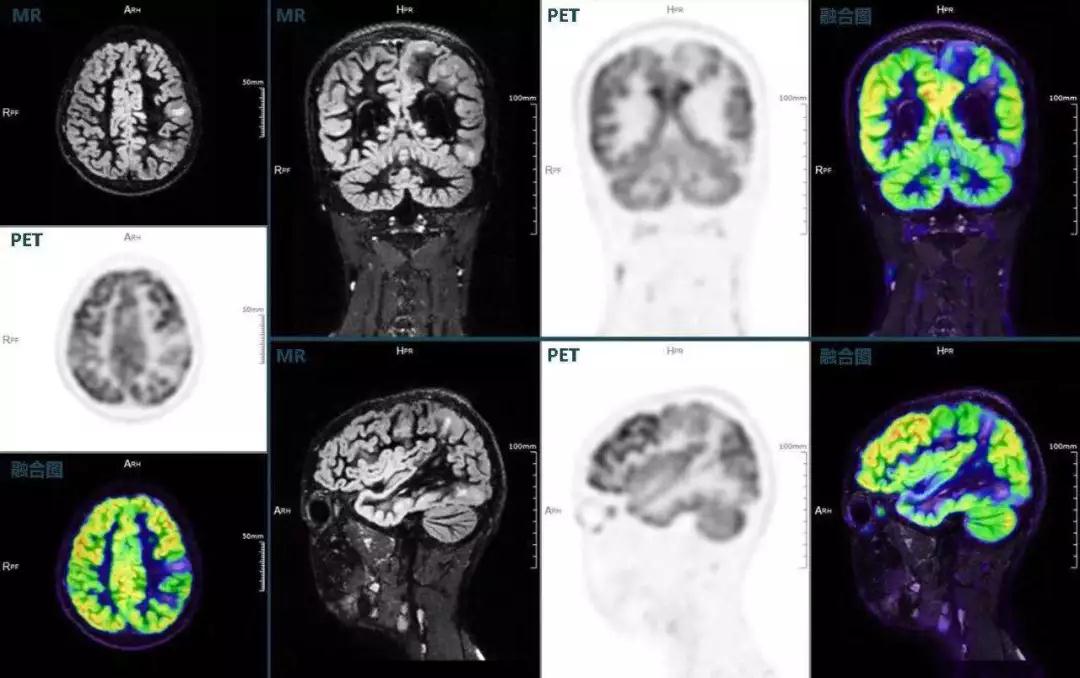

(结节性硬化,MR DIR序列清晰显示脑皮层病理改变,PET显示了病灶区域FDG的低浓聚。PET/MR融合显像同时提供了结构异常改变和功能变化的信息。)